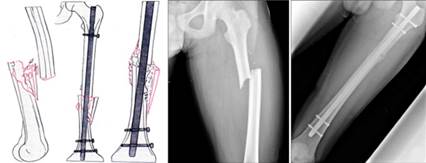

Эндопротезирование – хирургическая операция по замене изношенного или повреждённого сустава на искусственный аналог. Искусственный имплант состоит из трёх компонентов — головки, ножки, чашки. Головка двигается в чашке, как в естественном суставе. Детали изготавливают из сплавов металла, керамики или полимерных материалов [10].

Рисунок 2 Эндопротезирование

Особенности эндопротезирования:

- Протезирование бывает однополюсным (заменяется только один компонент сустава) или тотальным (заменяется весь сустав целиком).

- Тип, модель и размер протезной конструкции подбираются индивидуально в каждом клиническом случае.

- В крупных операциях применяются системы компьютерной навигации и 3D-моделирования для точного подбора имплантатов [1].

Эндопротезирование бывает первичным и ревизионным. Первое проводится при первичном поражении сустава, а второе – при износе, расшатывании и осложнениях ранее установленного протеза [4]. Его используют при выраженных дегенеративно-дистрофических заболеваниях суставов (в частности, при артрозах), тяжелых травматических повреждениях с разрушением суставных поверхностей, асептическом некрозе костной ткани, и в случаях, когда обычное лечение не обеспечивает полноценного восстановления функции сустава [3].